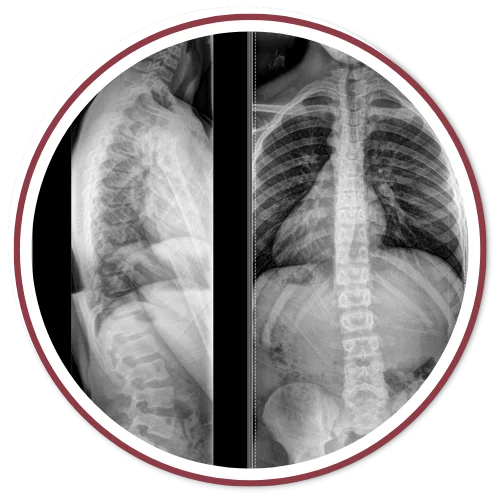

The Gonstead Technique relies on five essential components: Thorough Health History, Postural Assessment, Instrumentation, Palpation, and X-Rays. By integrating these elements, we can pinpoint the precise location that requires an adjustment. When all these factors align, we can provide the patient with a specific and effective adjustment. Specificity is the key, as Dr. Gonstead emphasized that three adjustments on the wrong vertebral segment could lead to a Subluxation, highlighting the importance of precision.

According to the Gonstead methodology, understanding that subluxations originate from the disc is crucial. Recognizing the stages of disc degeneration is essential for determining the appropriate adjustment direction and force needed for effective correction.

Dr. Gonstead's Level Disc Theory asserts that "anatomically and physiologically normal discs promote optimum vertebral alignment." This is evidenced when the vertical height of a vertebral couple is uniform around 360 degrees, with the vertebral bodies properly aligned. This alignment, known as "Parallel Discs," ensures even weight distribution, adequate nutrient flow, and optimal joint function and movement within the spine.